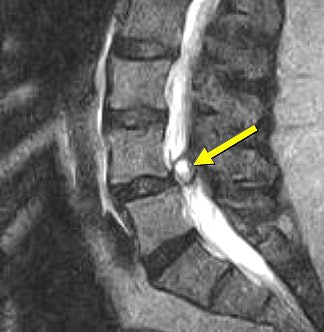

| Above, nonaxial-loaded images. Below, axial-loaded images. Increase in stenosis at L4 level by 2.0 mm and left L4 spinal nerve root with axial loading. All images courtesy of Dr. Gerald Anzalone. |